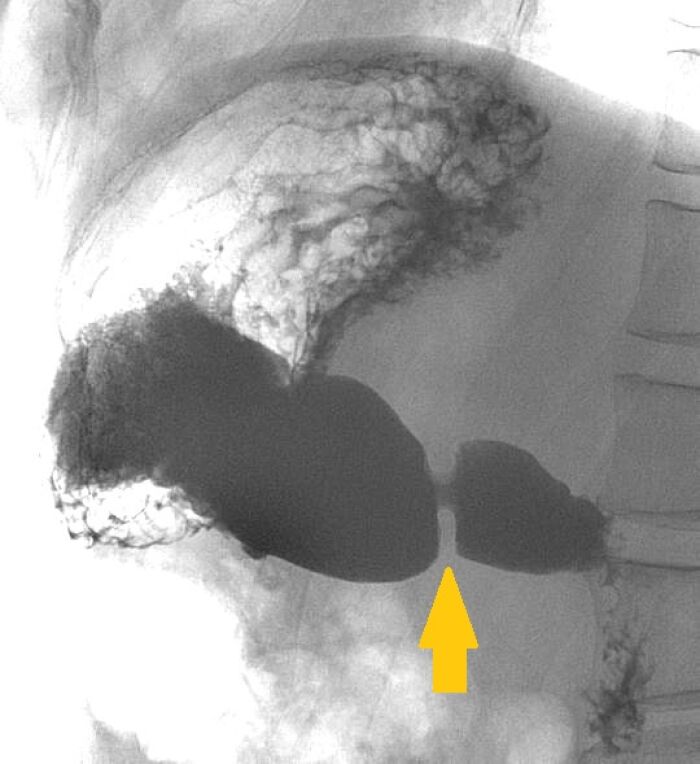

El píloro es una abertura en la parte inferior del estómago que controla el paso de los alimentos hacia los intestinos.

Actúa como una válvula que regula el flujo de los alimentos digeridos, evitando que ingresen de forma brusca al intestino delgado.

El píloro es una estructura anatómica ubicada en la parte inferior del estómago, que actúa como una válvula que regula el paso de los alimentos digeridos hacia el intestino delgado. Esta abertura se encarga de permitir el paso controlado de los alimentos parcialmente digeridos, evitando que grandes cantidades de comida ingresen al intestino delgado de manera abrupta.

El píloro cumple un papel fundamental en el proceso de digestión, ya que regula el flujo de los alimentos hacia el intestino delgado, donde se completa la absorción de nutrientes. Además, su función contribuye a mantener un equilibrio en la liberación de los alimentos digeridos, permitiendo que el sistema digestivo realice su labor de manera eficiente.

En condiciones normales, el píloro se contrae para evitar el paso descontrolado de los alimentos hacia el intestino delgado, lo que permite que estos sean procesados adecuadamente antes de continuar con su viaje a través del sistema digestivo. Sin embargo, ciertas condiciones médicas pueden afectar el funcionamiento del píloro, dando lugar a trastornos como la estenosis pilórica o el síndrome pilórico, que pueden interferir con la correcta evacuación gástrica.